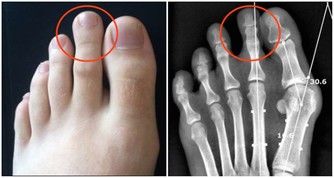

我們大家都知道,在我們呼吸的空氣當中有許多的雜質,比如灰塵、沙塵等等,鼻毛就像是一道屏障一樣,

鼻毛能夠有效過濾外界的雜質,防止灰塵進入到我們的身體當中,損傷我們的肺部健康,這一點是保護肺臟的作用。我們的身體離不開呼吸,24小時裡鼻腔都在進行工作,